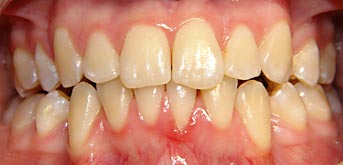

- Fotos der Zähne

Vergleich – vor der Behandlung – nach der Behandlung

Festhalten von Schäden und Flecken auf den Zähnen